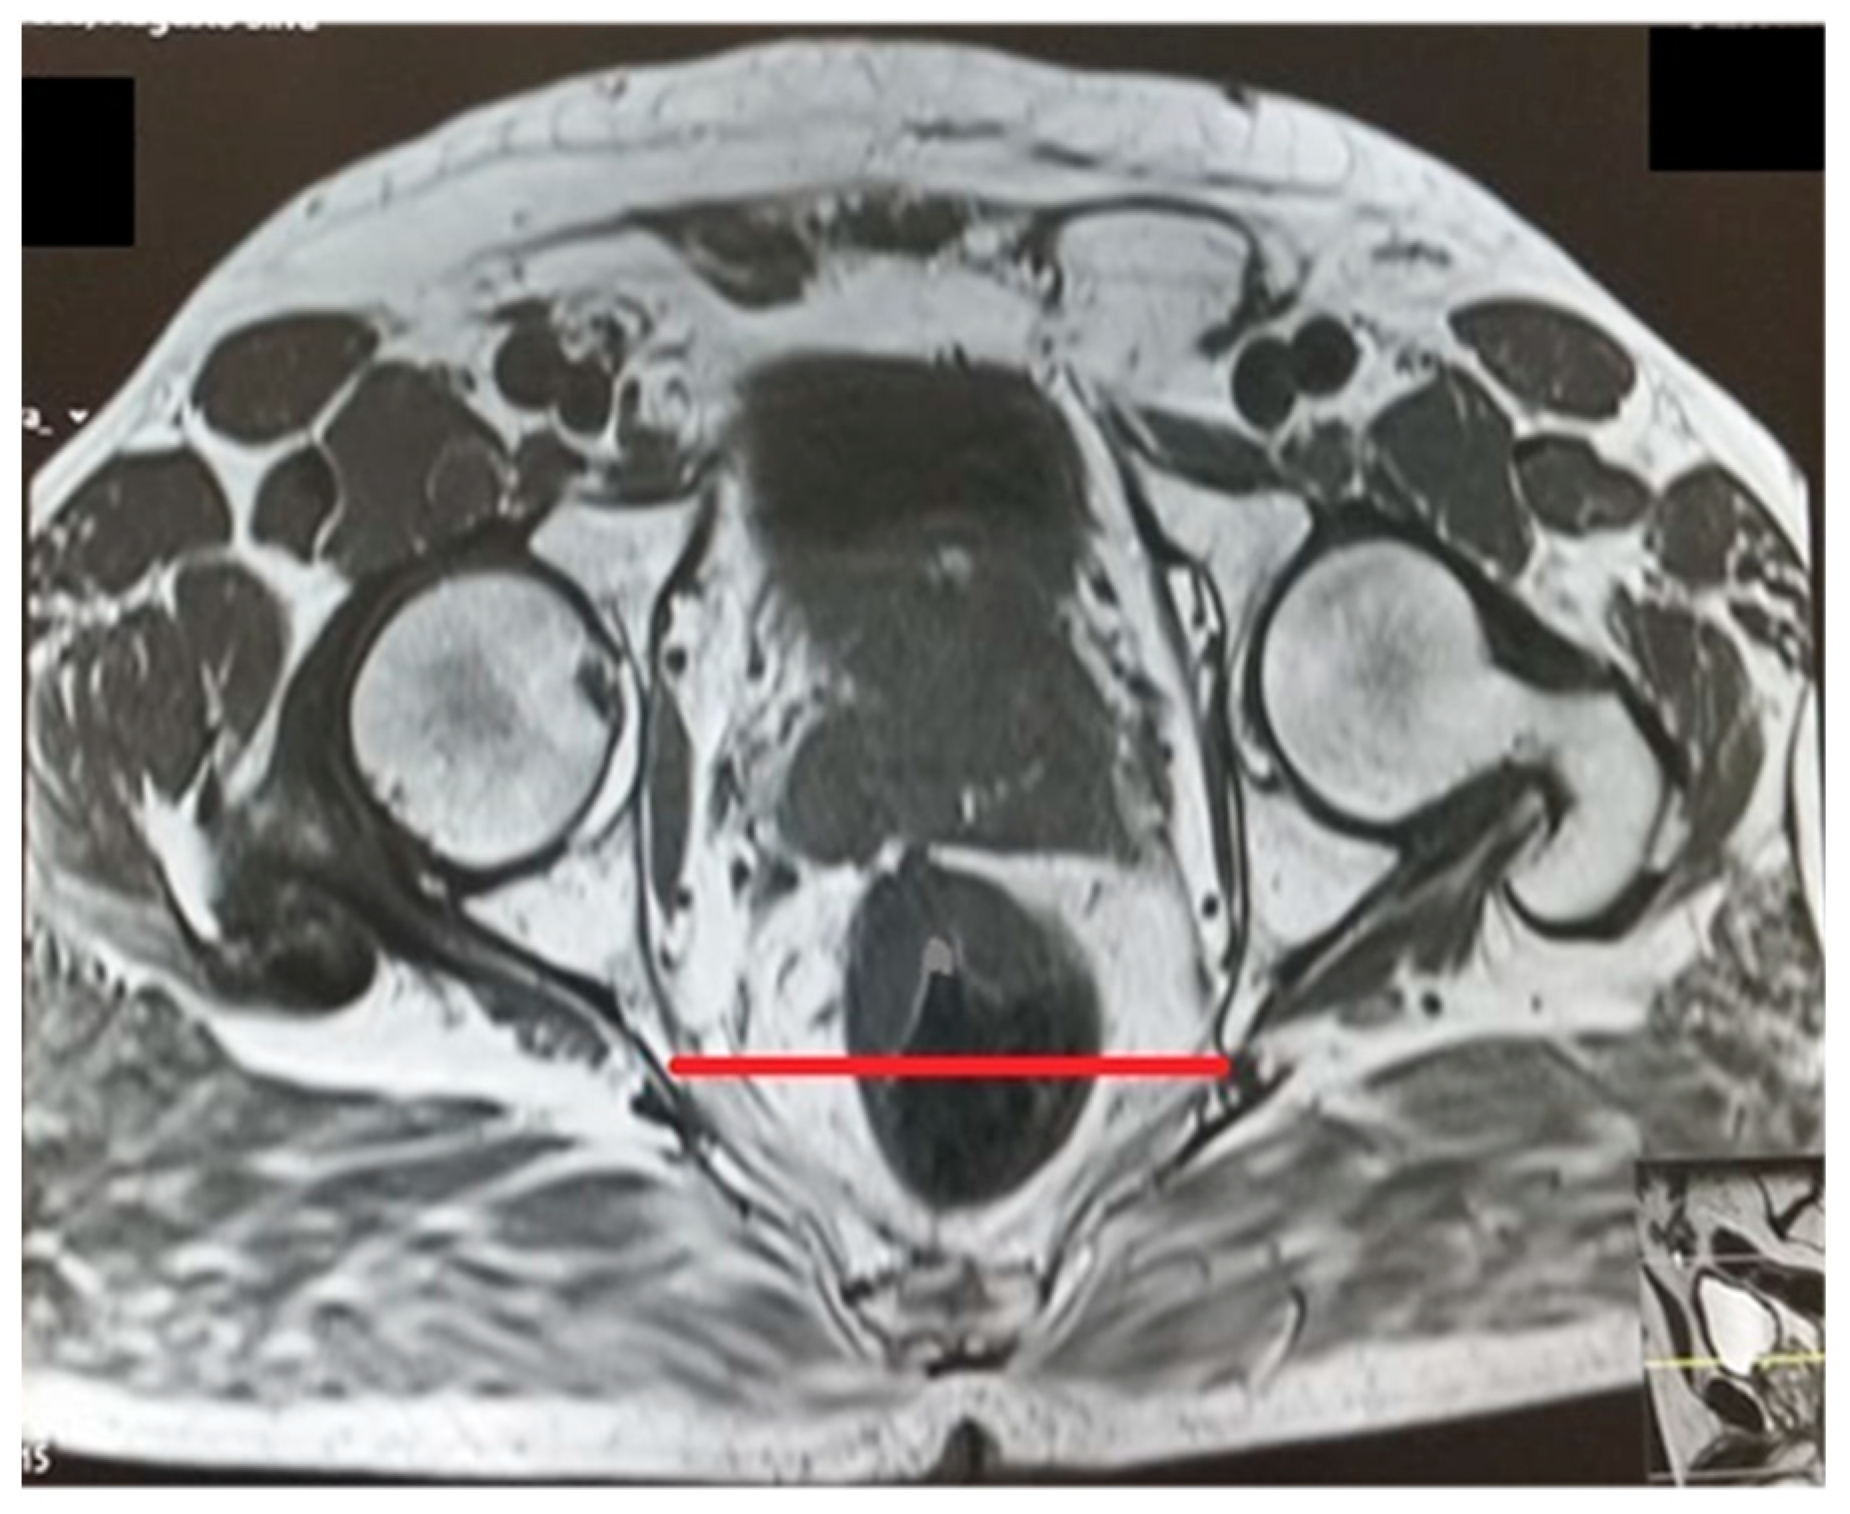

Intertuberous distance.

Figure 6.